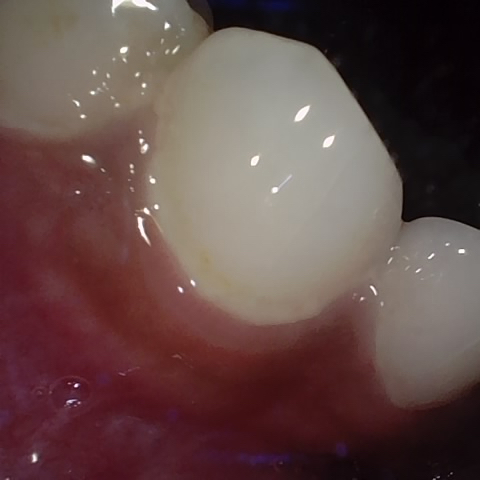

Annotated as "Bad"